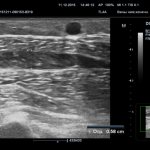

— Существуют ли степени сложности заболевания, когда поможет профилактика, когда — медикаменты, а когда — только хирургическое вмешательство? — Это зависит от самого тромба. Если он флотирующий, т. е. есть неприкрепленный элемент в просвете вены, есть высокий риск того, что он оторвется, особенно если он больше 7 см. В таких случаях нужна госпитализация и операция. Тромбы же малой протяженности, надежно прикрепленные к стенкам сосуда, лечатся медикаментозно. Но для того чтобы выявить тип тромба, обязательно нужно пройти обследование, сделать УЗИ или МРТ сосудов и начать лечение.

Когда в сосудах формируются холестериновые бляшки, то к ним прилипает кровяной тромб. Когда он вырастает большим, то отрывается и «путешествует» по кровеносной системе. Когда тромб закупорит сосуд головного мозга, то случится инсульт. Если поразит сосуд сердцаинфаркт. Если кровяной тромб перекроет артерию в лёгких, то человек умирает. Врачи с помощью УЗИ обнаруживают разросшийся тромб, от которого может оторваться тромб. Тогда человека спасёт операция. Сердечно-сосудистый хирург вставляет в сосуд фильтр, который перехватывает опасный сгусток.

• Дуплексное сканирование. С его помощью создается визуализация сосудов и исследуется кровоток.